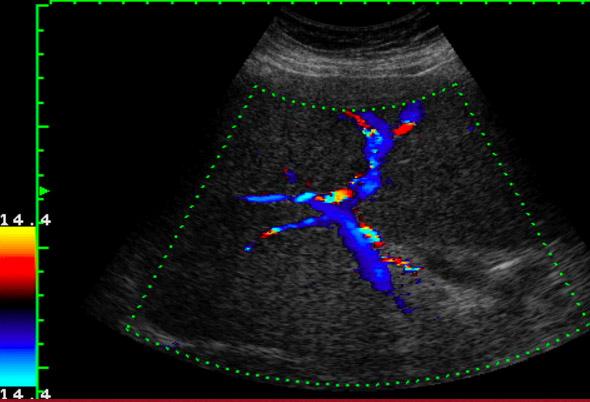

Portal Hypertension

Portal Hypertension

Portal vein Thrombosis - cavernous transformation

replacement of the normal single channel portal vein with numerous tortuous venous channels.

# cause of portal hypertension

Schistosomiasis

#1 cause of portal hypertension in the world. Not common in US but estimated 400,000 infected people have immigrated

parasitic infection mainly in Egypt

- irregular surface of liver

- hyperechoic thickened walls of portal venules giving the "clay-pipestem" pattern of periportal fibrosis

- marked thickening and echogenecity of the gallbladder bed

- splenomegaly

- portal vein and splenic vein dilatation with maintained continuous hepatopetal flow and average velocity